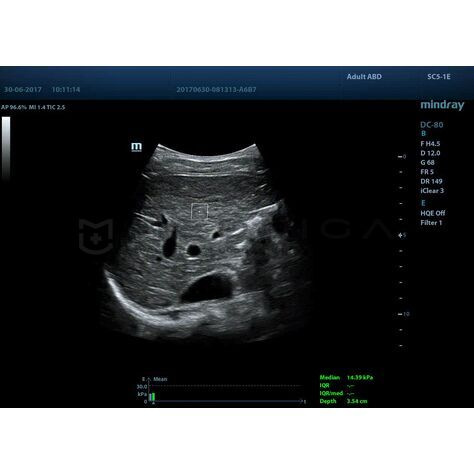

STQ (Sound Touch Quantification)

Sound Touch Quantification (STQ) позволяет быстро в режиме реального времени оценить жесткость ткани печени и определить стадию фиброза.